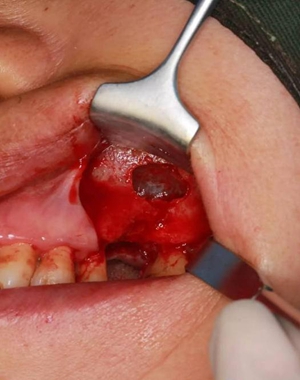

六個(gè)月之后